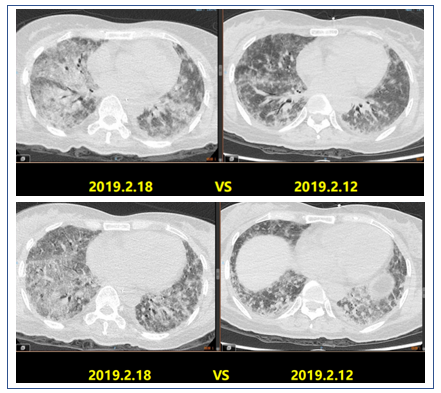

2019年2月1日患者胸部CT显示,上肺渗出进展(图14)。

此患者这一阶段肺内渗出病灶明显增多,可以从三方面考虑:①目前患者的原发病依然没有明确;②激素减量太快;③继发感染,如PCP,如果G试验阴性,则此种可能性偏小。

2019年2月25日患者胸部CT示双肺病变较前吸收(图16)。